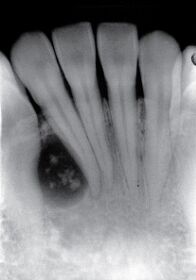

21.下列疾病何者的影像學最不可能出現如圖所示之病灶? (A)腺瘤樣齒源性瘤(adenomatoid odontogenic tumor) (B)造釉細胞瘤(ameloblastoma) (C)鈣化上皮齒源瘤(calcifying epithelial odontogenic tumor) (D)齒質性鬼細胞瘤(dentinogenic ghost cell tumor)

23.根據所附的根尖放射線影像,下列何者是最不可能的診斷?(A)殘餘囊腫(residual cyst) (B)單囊性造釉細胞瘤(uncystic ameloblastoma) (C)齒源性角化囊腫(odontogenic keratocyst) (D)骨化纖維瘤(ossifying fibroma)